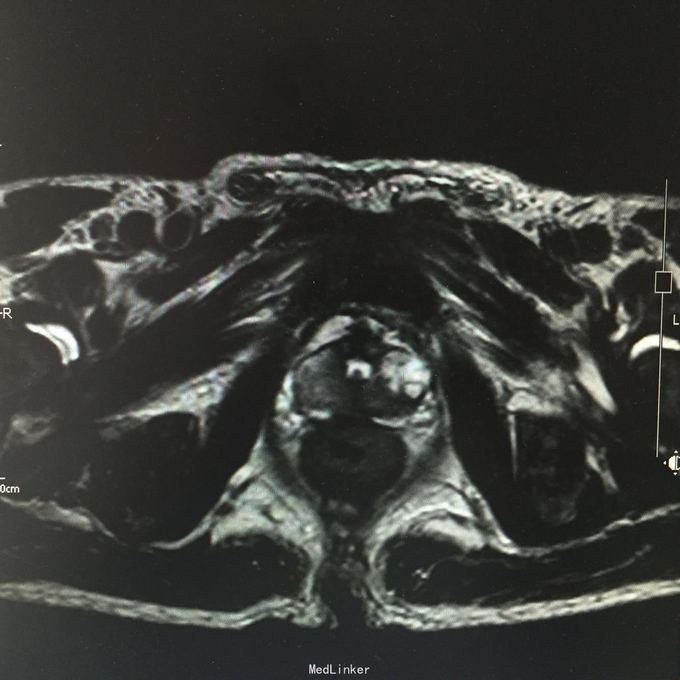

total PSA>100;前列腺磁共振平扫示:前列腺外周带左后方肿块,DWIBS信号明显增浓,考虑前列腺Ca。 行会阴前列腺穿刺活检术,病理示:前列腺腺癌。 全身骨扫描示:超级骨显像,符合前列腺Ca并多发骨转移。